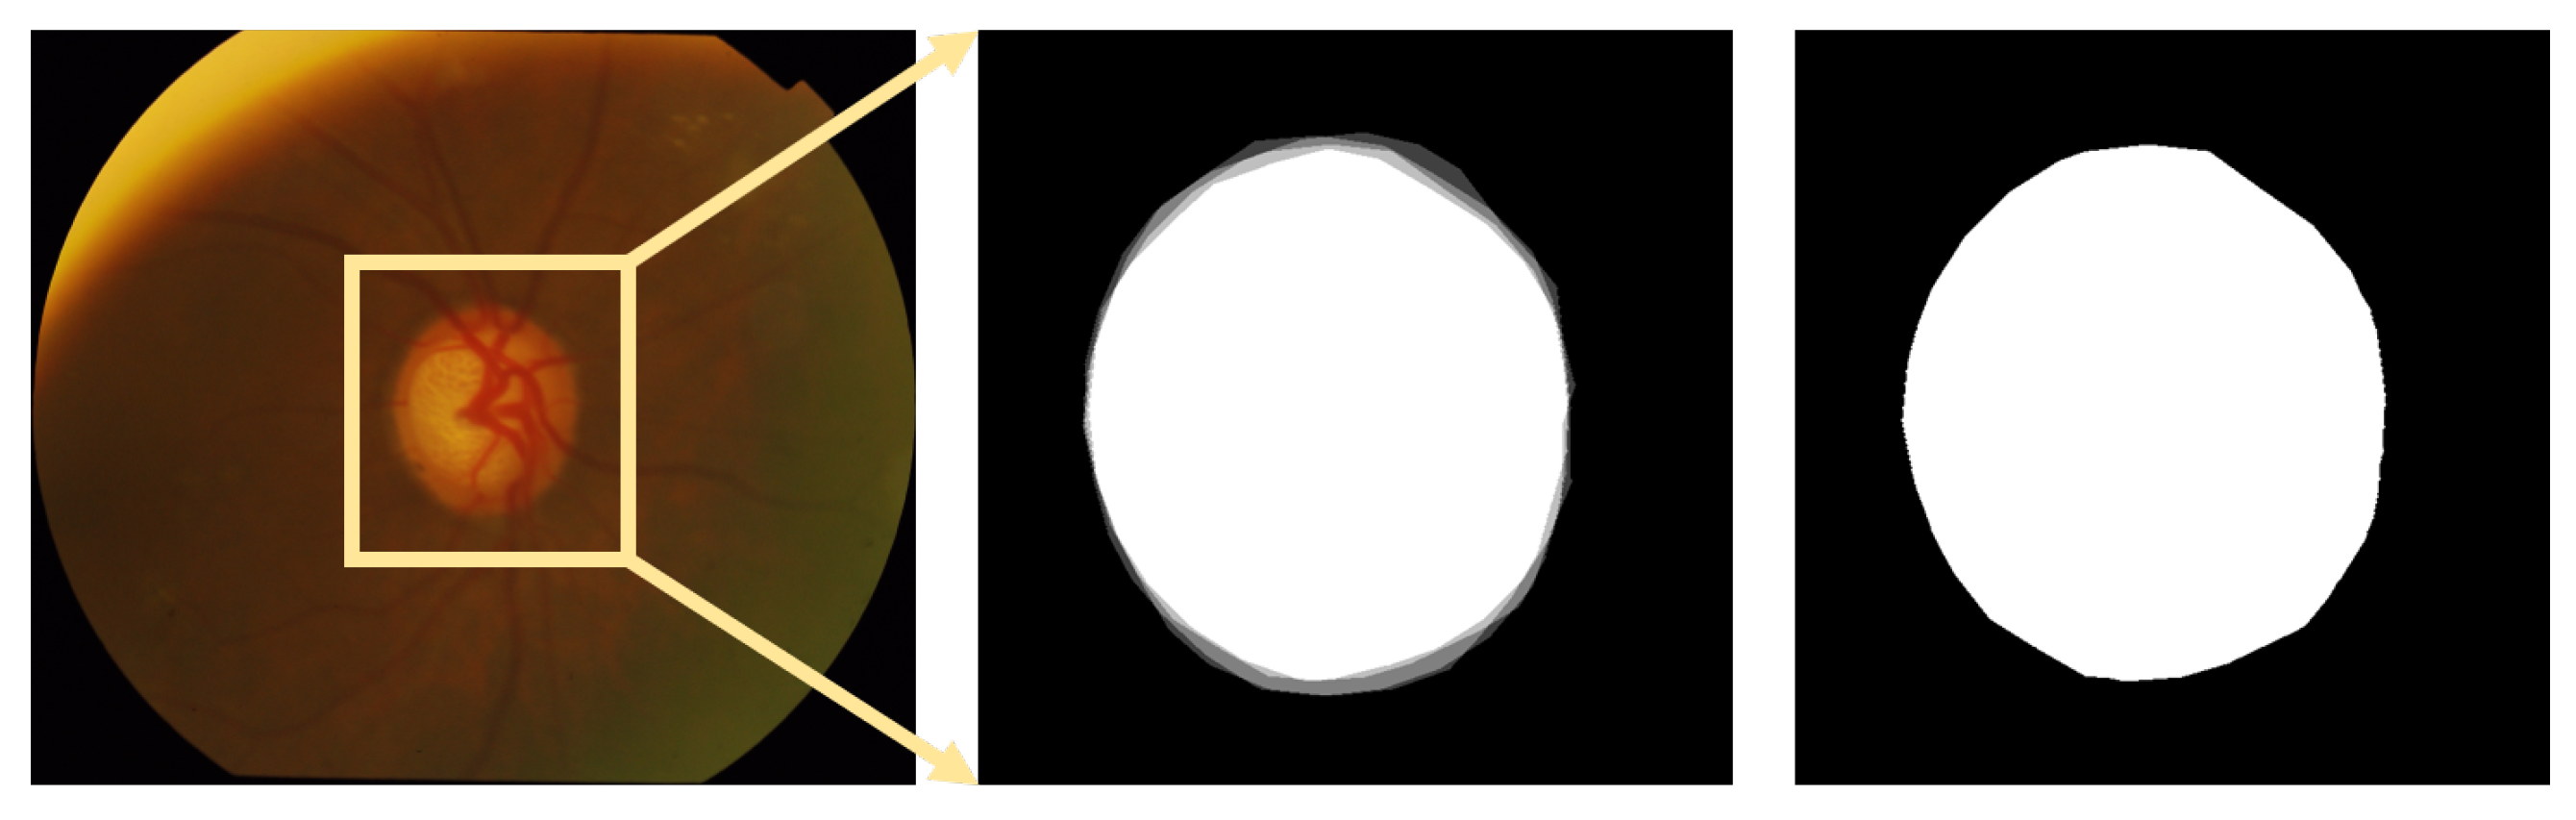

3.2.1. Region of Interest (ROI) Detection

- Step 1: Extracting the green channel (Figure 9b and 10b) from the RGB color space and inverting it (Figure 9c and 10c). In order to take advantage of the feature of high vascular density, it is necessary to roughly segment the blood vessels. In fundus images, blood vessels have a high contrast in the green channel, which is why the green channel is extracted. However, blood vessels are darker than those in other areas in the green channel. Thus, for using morphological top-hat transformation to segment blood vessels, the green channel is inverted.

- Step 3: Finding several circular areas with the highest vascular density (Figure 9e and 10e). The radius of circular areas is the average OD radius. Because of the rough and imprecise blood-vessel map, selecting only a few areas may not include OD. Thus, 20 circular areas were selected in this paper.

- Step 5: Extracting the rough ROI (Figure 9g and 10g) by this circular area. The side length of rough ROI is 4 times the average diameter of OD and the center of rough ROI is the center of circular area. As shown in Figure 11, there was still an error (the OD was not located at the center of ROI image) if locating OD only on the basis of high vascular density and high brightness.